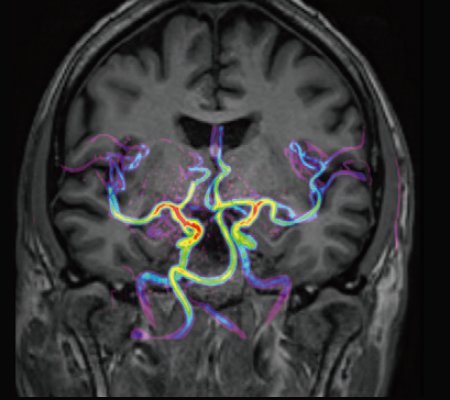

• Kopplung von mUTE und mASTAR ermöglicht 4D-Angiografie mit Auflösung einer TOF ohne Kontrastmittelgabe

KI-optimiertes Arbeiten und modernste 3T-Technologie machen den Vantage Galan 3T von Canon Medical aus. Canons KI-Anwendung AiCE, kurz für Advanced intelligent Clear-Imagequality Engine, entfernt intelligent das Rauschen und führt zu einer Verbesserung des SNR (Signal-Rausch-Verhältnis). Mit Hilfe der Deep Learning Technologie gelingen besonders klare und deutliche Bilder. Insgesamt ermöglicht die KI-Unterstützung des Vantage Galan 3T somit nicht nur eine höhere Auflösung der Bilder, sondern verkürzt in vielen Fällen auch die Aufnahmezeit.

Mit der PURERF-Technologie und der PUREGradienten-Technologie werden das SNR um bis zu 20% verbessert und Diffusionsbilder optimiert.